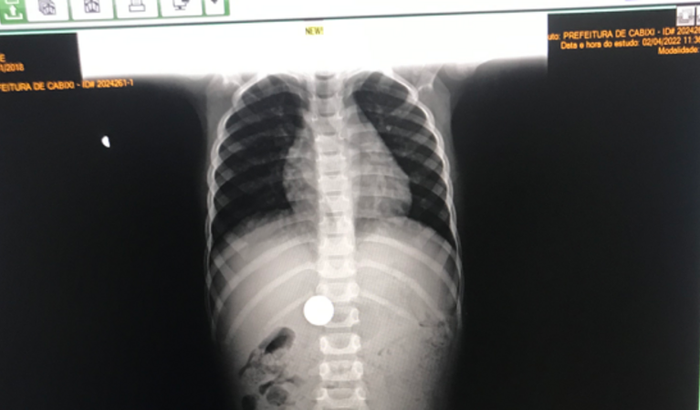

Olá,sou mãe do Pedro Henrique silva murari 3anos, ele engoliu uma moeda 1$ .pois já se passou 30dias vai precisar de cirurgia. Gostaria de colocar mais imagens,mas a plataforma não está permitindo